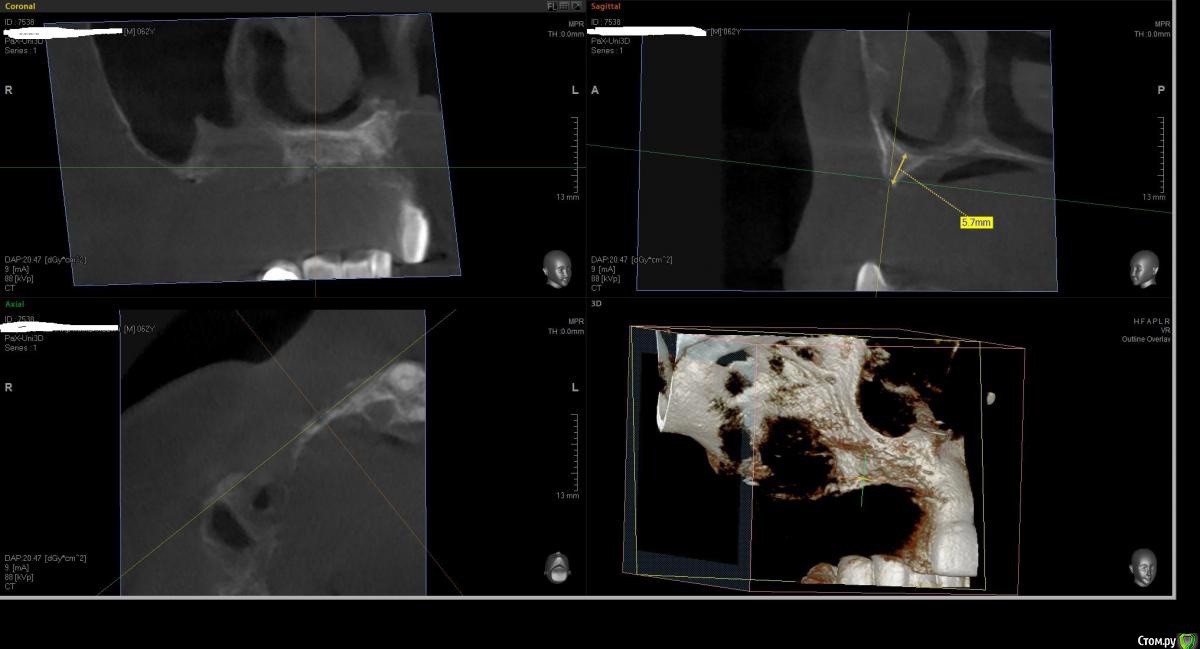

Kostoprav Опубликовано 1 августа, 2016 Поделиться Опубликовано 1 августа, 2016 что бы вы сделали в данной ситуации уважаемые коллеги? был синус и титановая сетка во фронте но увы все прокисло ((( 1 Ссылка на комментарий

Kostoprav Опубликовано 2 августа, 2016 Автор Поделиться Опубликовано 2 августа, 2016 Всё вычистить, подождать заживление и повторить.это кт уже после чистки, а повторить снова титановой сеткой?думаю снова сетка здесь не прокатит( Ссылка на комментарий

Kostoprav Опубликовано 3 августа, 2016 Автор Поделиться Опубликовано 3 августа, 2016 скисло через 3 мес, до этого все было идеально!но меня больше беспокоит вопрос что теперь с этим делать, там теперь кости особенно во фронте почти нет.какую технику использовать? Ссылка на комментарий

kriokov Опубликовано 9 августа, 2016 Поделиться Опубликовано 9 августа, 2016 Зигомы...х\з , там по их по две с каждой стороны надо, если только на зигомах ( фо фронте с костью жиденько)но если опыт работы с ними есть - то вариант Ссылка на комментарий

Bier Опубликовано 9 августа, 2016 Поделиться Опубликовано 9 августа, 2016 конечно по 2 зигомы с каждой стороны. На мой взгляд - вариант для этой ситуации. С фронтом ничего не делать, там базис протеза будет Ссылка на комментарий

Kostoprav Опубликовано 9 августа, 2016 Автор Поделиться Опубликовано 9 августа, 2016 С левой стороны кость есть, или туда тоже зигомы? Ссылка на комментарий

kriokov Опубликовано 9 августа, 2016 Поделиться Опубликовано 9 августа, 2016 Kostopravесли есть возможность залейте просто реформат оптг верхней челюсти , Ссылка на комментарий